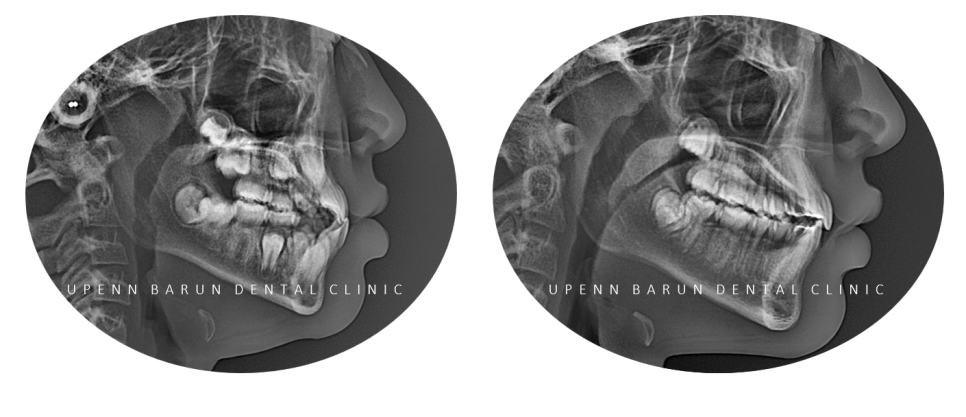

이 환자분은

유펜바른치과에서 진단한 결과

치아의 배열이나 위치에 문제가 있고

반대교합이 골격적으로 심한 정도가 아니셔서

#인비절라인퍼스트 로 반대교합을 해결하기에 적합한 증례였답니다 :)